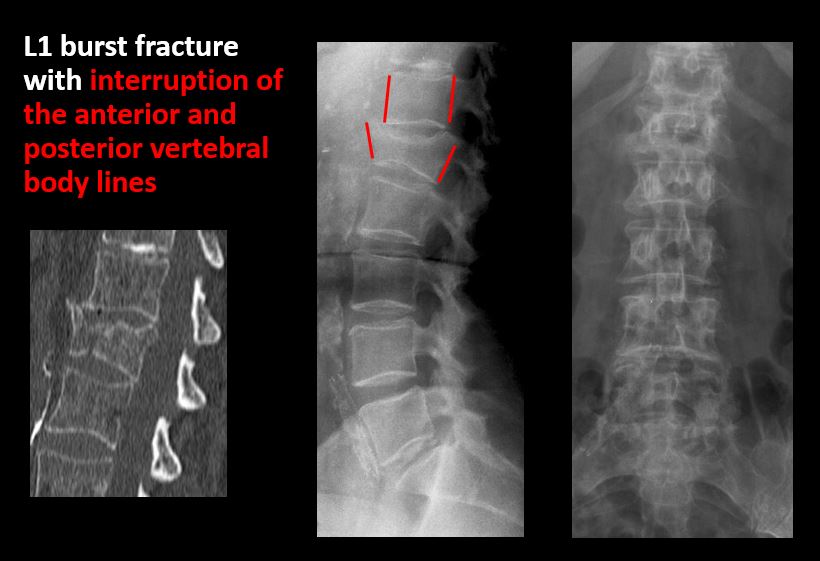

The anterior and posterior vertebral body lines are abnormal or interrupted. |

Yes | NA |

There is a fracture or distraction of a vertebral body, transverse or spinous process, or other posterior element. |

There is anterior wedging and/or compression of a vertebral body or end plate. |

There is an end plate avulsion or other fracture. |

There is an abnormality of a pedicle or lamina on the frontal or lateral view. |

There is a fracture, erosion, sclerosis, lytic, or blastic lesion of a pedicle or lamina. |